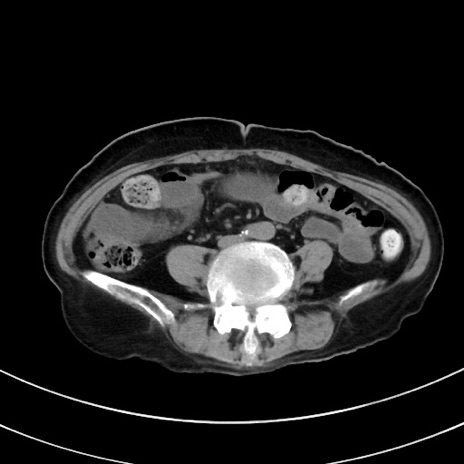

症例33(横断像)

【症例】70歳代 女性

【主訴】心窩部痛

【現病歴】延髄病変の精査・加療にて神経内科入院中。本日より心窩部痛あり。

【身体所見】右下腹部を中心に圧痛と反跳痛あり。

【データ】WBC 10900、CRP 0.02